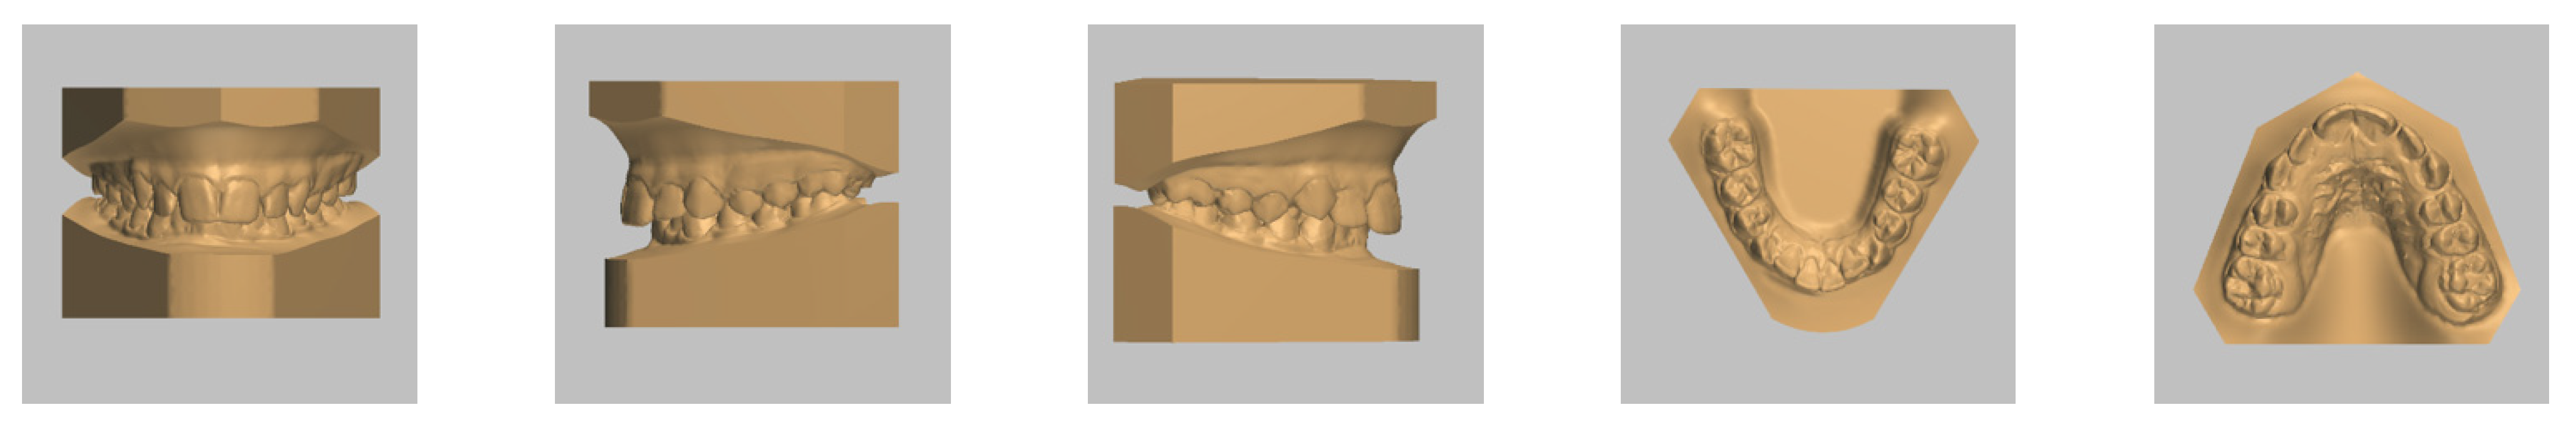

4. Case Report

4.1. Etiology and Diagnosis

4.3. Treatment Strategy

4.4. Treatment Progress